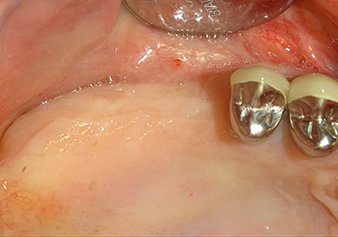

49-летняя пациентка, некурящая и не имеющая ничего примечательного в общей истории болезни, была направлена в нашу хирургическую стоматологическую клинику для хирургического удаления зуба 16 и последующей имплантации. После удаления зуба пациентка перенесла синусит в легкой форме, в результате чего мы сначала выждали шесть месяцев перед проведением операции. Остаточная высота кости при запланированном положении имплантата составляла 3-4 мм (рис. 1 и 2).

Preoperative findings: The alveolar ridge has healed well, including sufficiently broad, keratinised gingiva

Рис.1: Предоперационные данные: Альвеолярный гребень хорошо зажил, включая достаточно широкую, кератинизированную десну.